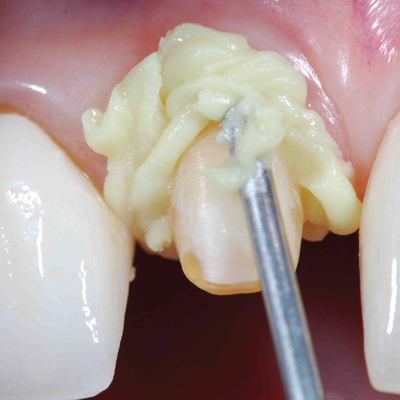

Crown & Bridge with Retraction Cap

Using a retraction cap with Traxodent for crown and bridge procedures simplifies moving the paste into the sulcus and provides an atraumatic method for greater retraction. The pressure from the cap quickens and assists hemostasis while the absorbent cotton cap soaks up the fluid in the sulcus. Additionally, the cap quickly brings Traxodent into close contact with the hemorrhaging tissue, which allows the astringent properties to work faster.

Photos courtesy of Dean Elledge, DDS, MS UMKC School of Dentistry

Crown & Bridge with Retraction Cord

Traxodent is ideal to replace the second cord in the double cord technique. This technique saves time and lessens the discomfort to the patient while providing greater retraction. Traxodent easily rinses away, eliminating the occurrence of break-through bleeding when removing the second cord.

Photos courtesy of Dean Elledge, DDS, MS

Loose Tissue

For difficult tissue that will not stay retracted, Traxodent can be used with retraction cord and cap.

Photos courtesy of William Crinzy, DDS MS UMKC School of Dentistry